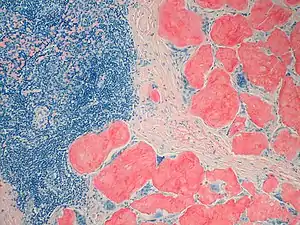

Amyloidosis, Node, Congo Red Amyloidosis, blood vessels, H&E

Amyloidosis, blood vessels, H&E Amyloidosis, lymph node, H&E